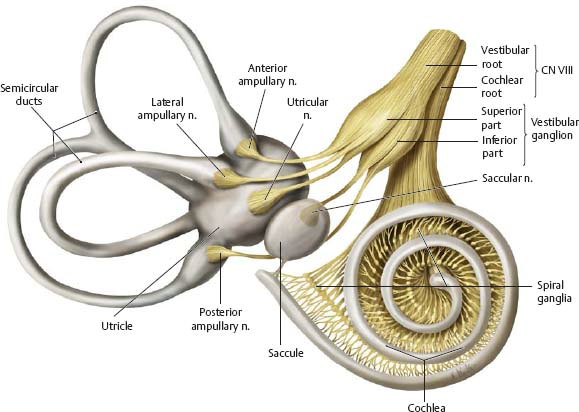

CN VIII

- Vestibular n. (平衡)

- Cochlear n. (聽力)